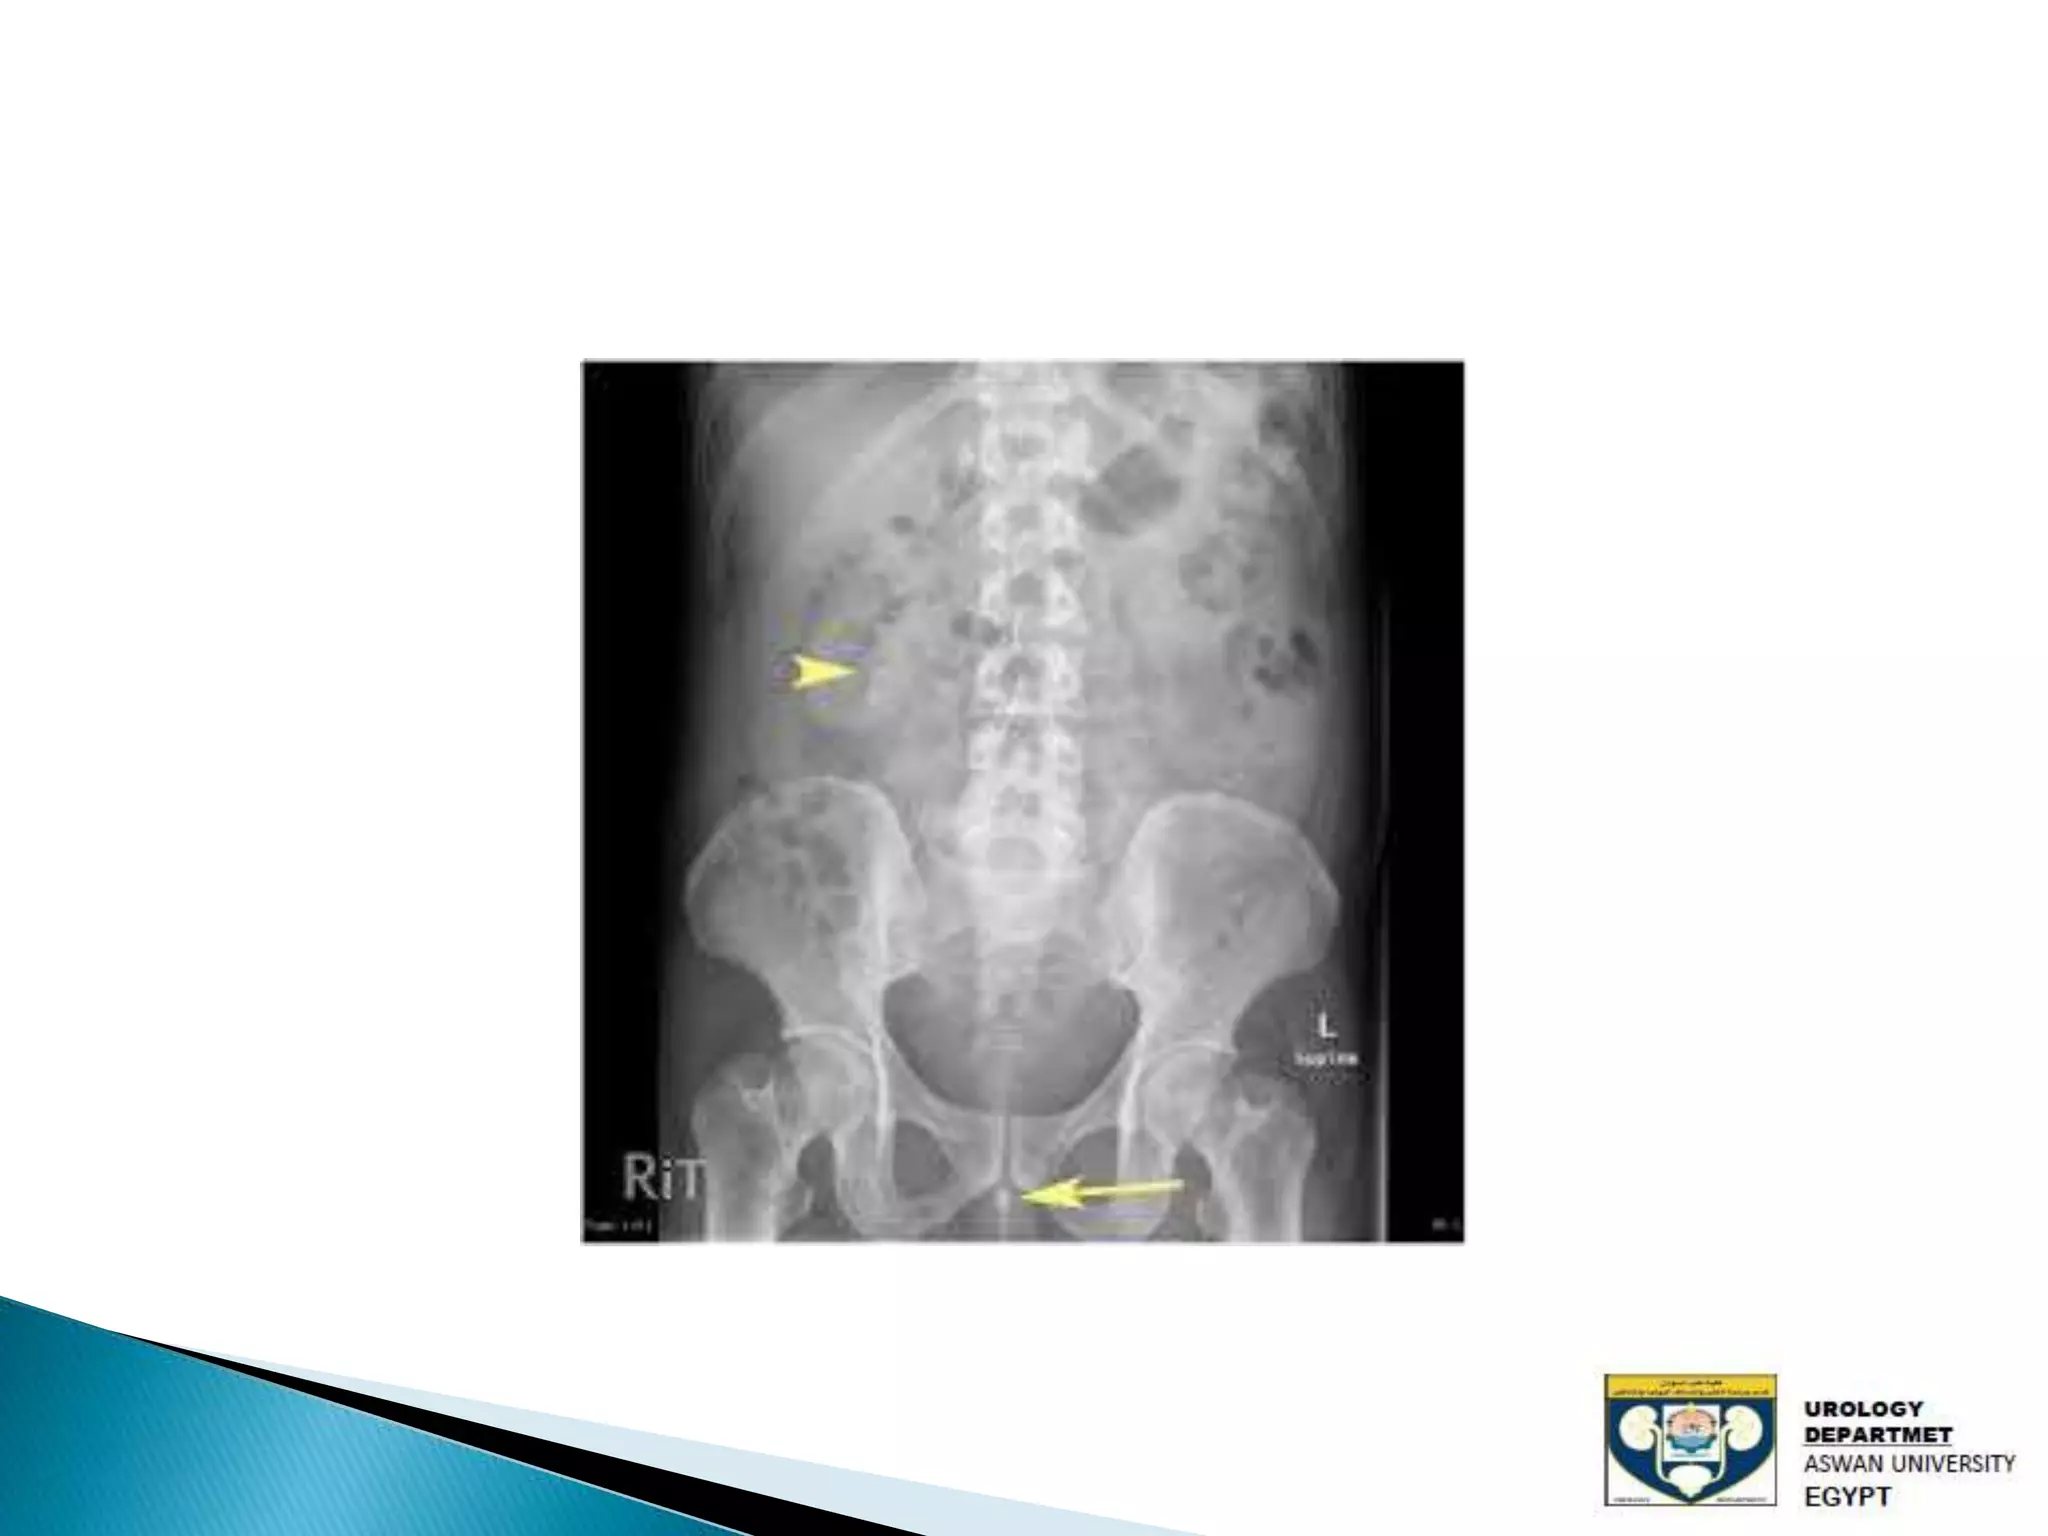

The document discusses urinary tract stones, detailing their types, causes, symptoms, and diagnostic methods. It highlights the risk factors such as infections and obstructions, with men being more commonly affected. Treatment options include various surgical methods, particularly for managing bladder outflow obstruction and lithiasis.